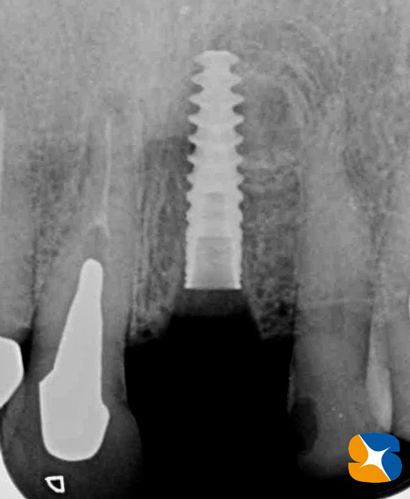

インプラント移植が完了したレントゲン。インプラントの半分位が上顎の骨で満たされていません。

使用インプラント:スプライン直径3.75㎜、高さ11.5㎜